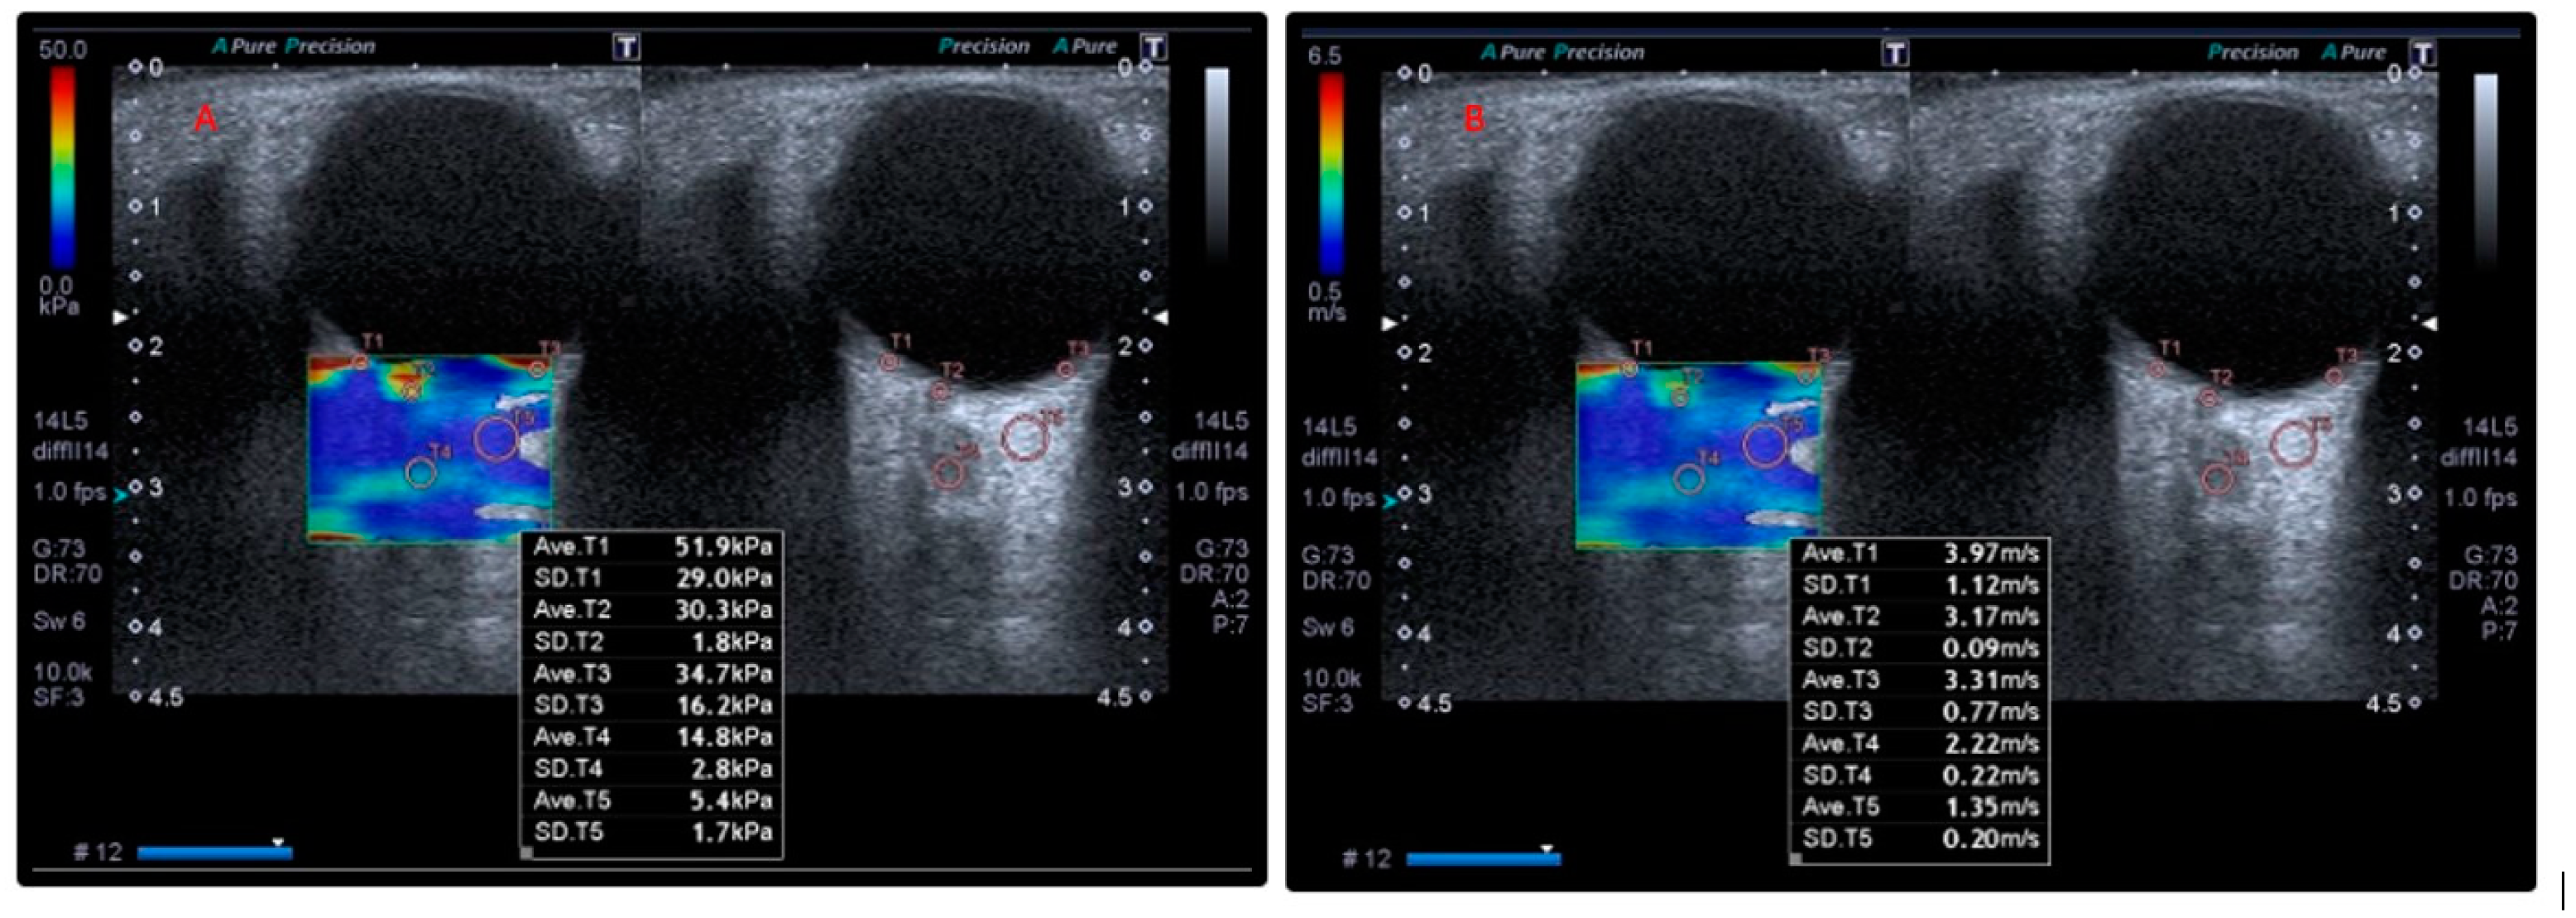

2.3. Orbital SWE Examination